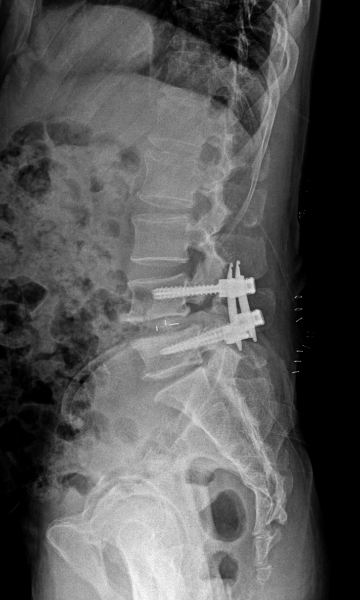

척추분리증 수술 전·후

2023.01.17

ㆍ환자 동의를 받은 자료이며, 이미지 사진은 실물과 다를 수 있습니다.

ㆍ모든 자료는 새움병원 자료입니다.